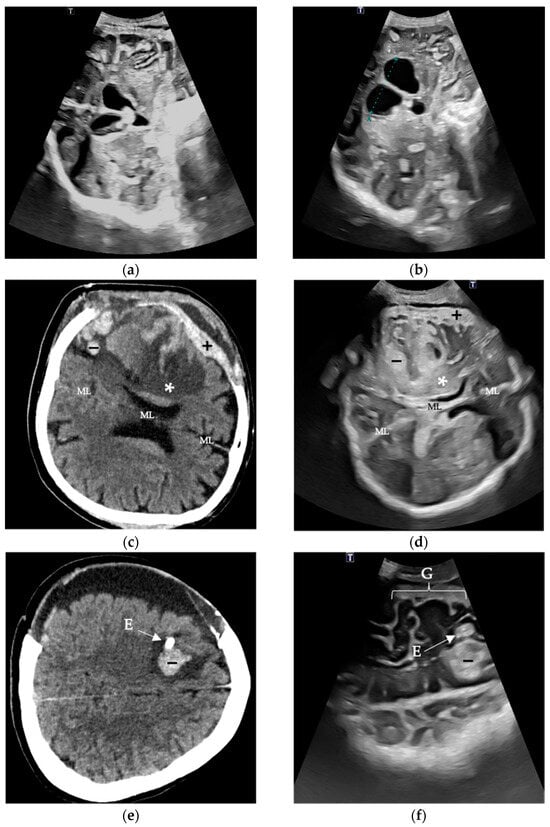

A collection of selected patient examples for evaluation of the predefined image markers is shown in Figure 1.

Figure 1.

Evaluation of predefined image markers in selected cases In the first case, the coronal view of the lateral ventricles and the third ventricle with opened EVD (a) and progression in ventricular growth after 24 h EVD closure (b) is shown. In the case of a hemorrhagic infarction in a 65-year-old patient, both the corresponding cranial CT (c) and the follow-up TUS examination (d) reveal infarcted brain tissue (*), a subtle subdural hemorrhage (+), as well as intracerebral hemorrhagic components (−). A relevant midline (ML) shift is not present. Finally, a cranial CT (e) and TUS (f) of a 41-year-old patient with spontaneous SAH is depicted. In this case, in order of EVD (E) implantation, a consecutive tract hemorrhage occurred that was evaluated daily. Also, gyration (G) with corresponding external cerebrospinal fluid spaces could be assessed via TUS in the absence of postoperative hemorrhage.

Different intracranial structures can exhibit varying echogenicity: gyri are mostly isoechogenic; cerebrospinal fluid (CSF) is hypoechogenic; and structures like the falx, sulci, and dura mater typically are hyperechogenic []. Unlike CT, ultrasound echogenicity, in some cases, can be angle-dependent (e.g., connective tissue), which can impact the assessment []. This can also be affected by pathologies with structural changes over time. Acute ICHs appear hyperechogenic, while older post-hemorrhagic changes often appear as hypoechogenic lesions []. During the resorption phase, varying echogenicities can be observed (as shown in Figure 1d,f).

Although the curved transducer is used routinely in several studies mentioned above, especially when depicting structures through the craniectomy defect, one disadvantage of using the curved transducer is that, particularly in cases of large defects (e.g., large CSF collections), the contact surface may be reduced, requiring increased pressure. This pressure may compress the skin, potentially redistributing underlying fluid and leading to its underestimation. An example of this can be seen in Figure 1e,f, where subdural and epidural CSF collections are evident on CT but only minimally visible on TUS. A relatively high examiner dependency of ultrasound in general is well known [].